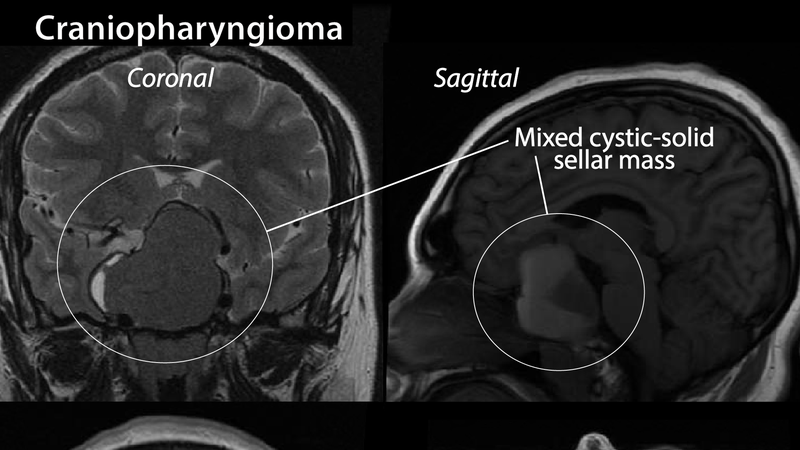

U sọ hầu (Craniopharyngioma) là các khối u lành tính hiếm khi xảy ra ở não. Các khối u này còn được gọi là “khối u túi Rathke”. Nó xuất hiện ở gần cuống tuyến yên - nơi tiết ra các hormone giúp kiểm soát một số chức năng của cơ thể. Các khối u này có cấu trúc đặc và hình thành chủ yếu do các mảng canxi và dung dịch. U sọ hầu có xu hướng phát triển khá chậm. Nếu tình trạng bệnh kéo dài, bệnh nhân có thể bị ảnh hưởng ở chức năng của tuyến yên và cơ quan lân cận.